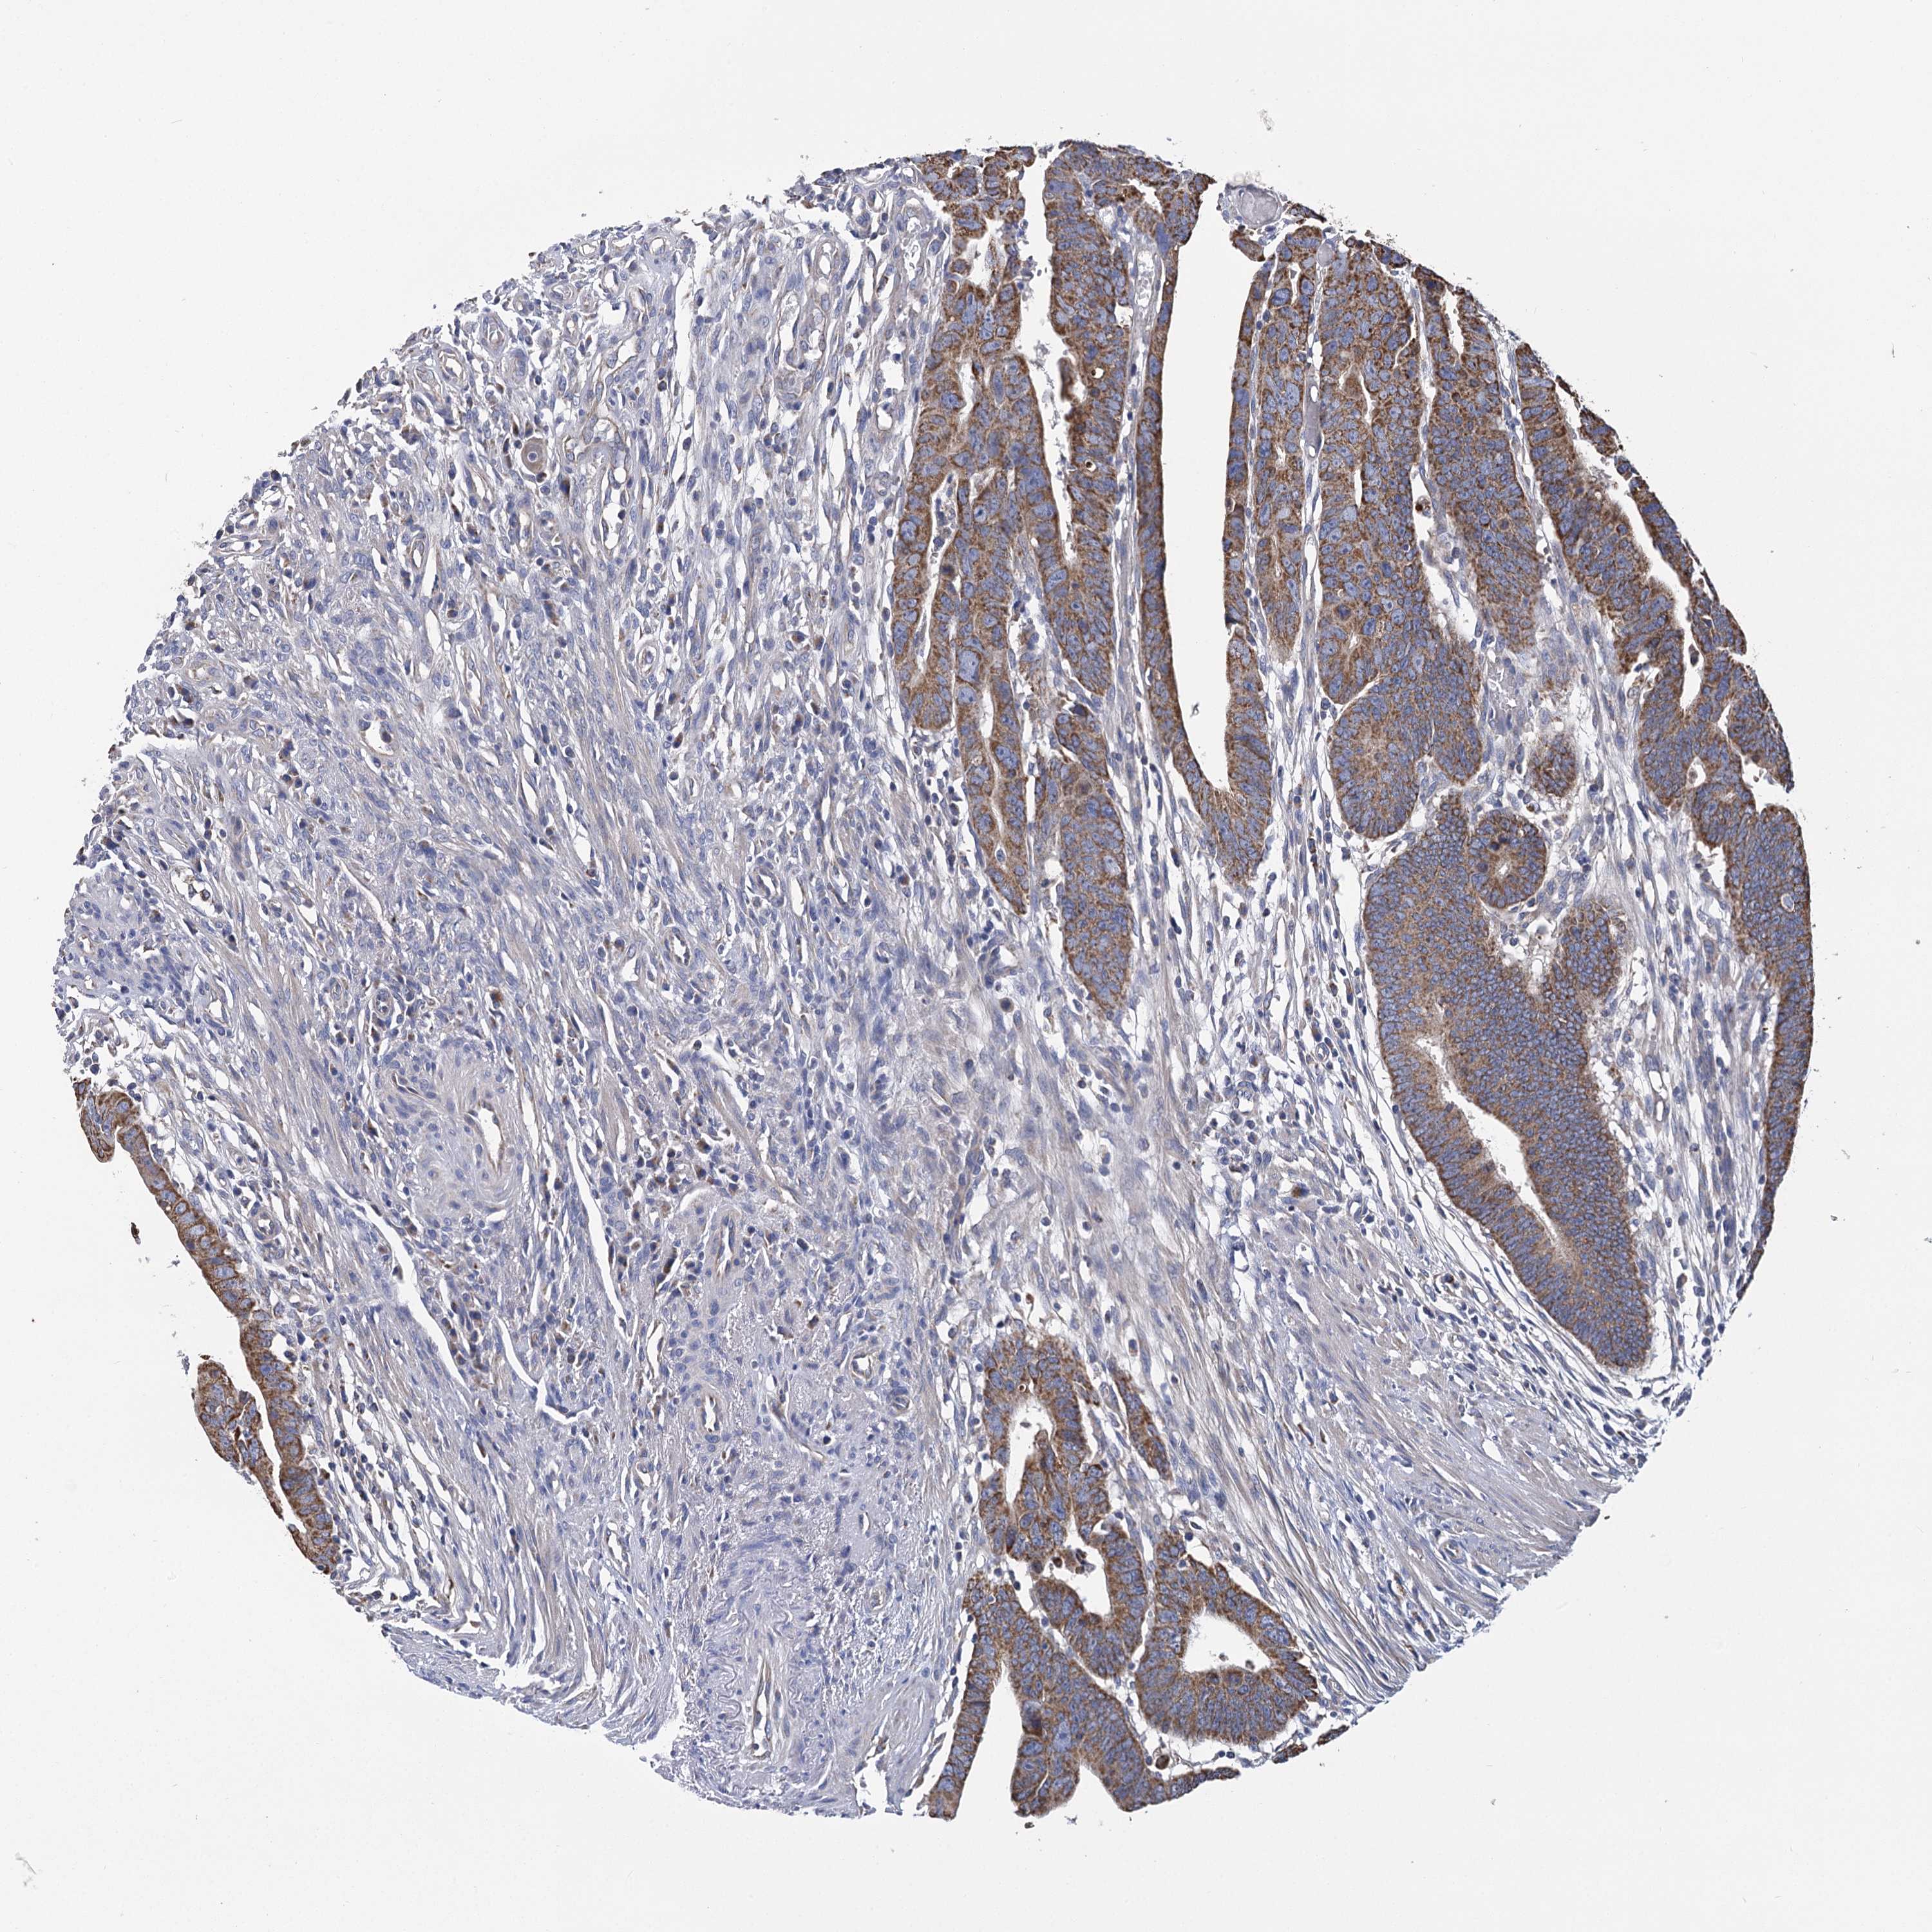

CANCER COLORECTAL CANCER Show tissue menu

Colorectal cancer

Human cancer

Colon adenocarcinoma